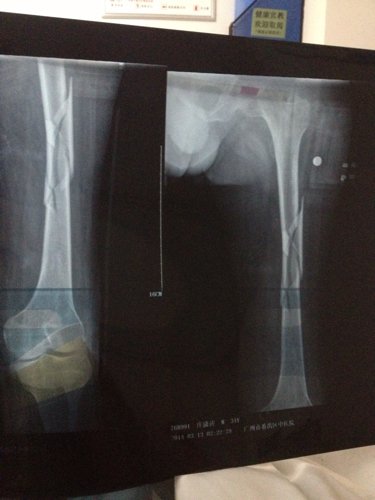

你好医生!左腿原来有小儿麻痹证,就在上个月11号不小心跌倒骨折13号做手术加钢板!现在在家休养 现 你好医生!左腿原来有小儿麻痹证,就在上个月11号不小心跌倒骨折13号做手术加钢板!现在在家休养。现在腰很痛?是怎么回事,有过性生活。现在简单吃两种药?请问医生像我这种情况会不会很难恢复原来那样?是不是还要吃些什么?还有要不要外敷些什么?还要腰很痛怎么办,谢谢! 点击展开 匿名用户 2014-04-08 09:50 为您推荐: 其他回答 病情分析: 你好,考虑是恢复期间的应急反应。 指导意见: 可以多食瘦肉、鱼、鸡蛋、牛奶、豆类食品以及新鲜蔬菜、水果等,注意逐渐恢复锻炼。 独水凡_xjeq 2014-04-08 10:51 相关问题 你好、请问:左小腿骨折做手术取钢板后可以同房吗?同房有影响吗?还是需要等的话要多久? 骨博士你好,我膝盖上面一点点骨折了,已经八个月了能取出钢板了吗 骑电动车把左股骨颈摔骨折了,而且左腿是小儿麻痹,女,年龄五十四岁,在家静养能康复吗?有什么好办法吗

你好医生!左腿原来有小儿麻痹证,就在上个月11号不小心跌倒骨折13号做手术加钢板!现在在家休养。现在腰很痛?是怎么回事,有过性生活。现在简单吃两种药?请问医生像我这种情况会不会很难恢复原来那样?是不是还要吃些什么?还有要不要外敷些什么?还要腰很痛怎么办,谢谢!